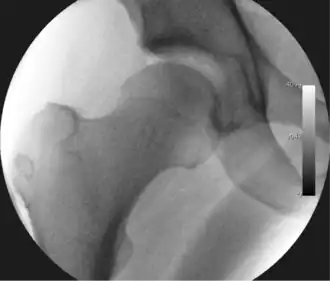

Figure 3. Fluoroscopic picture showing a mild amount of distraction of the hip before insertion of any instruments -